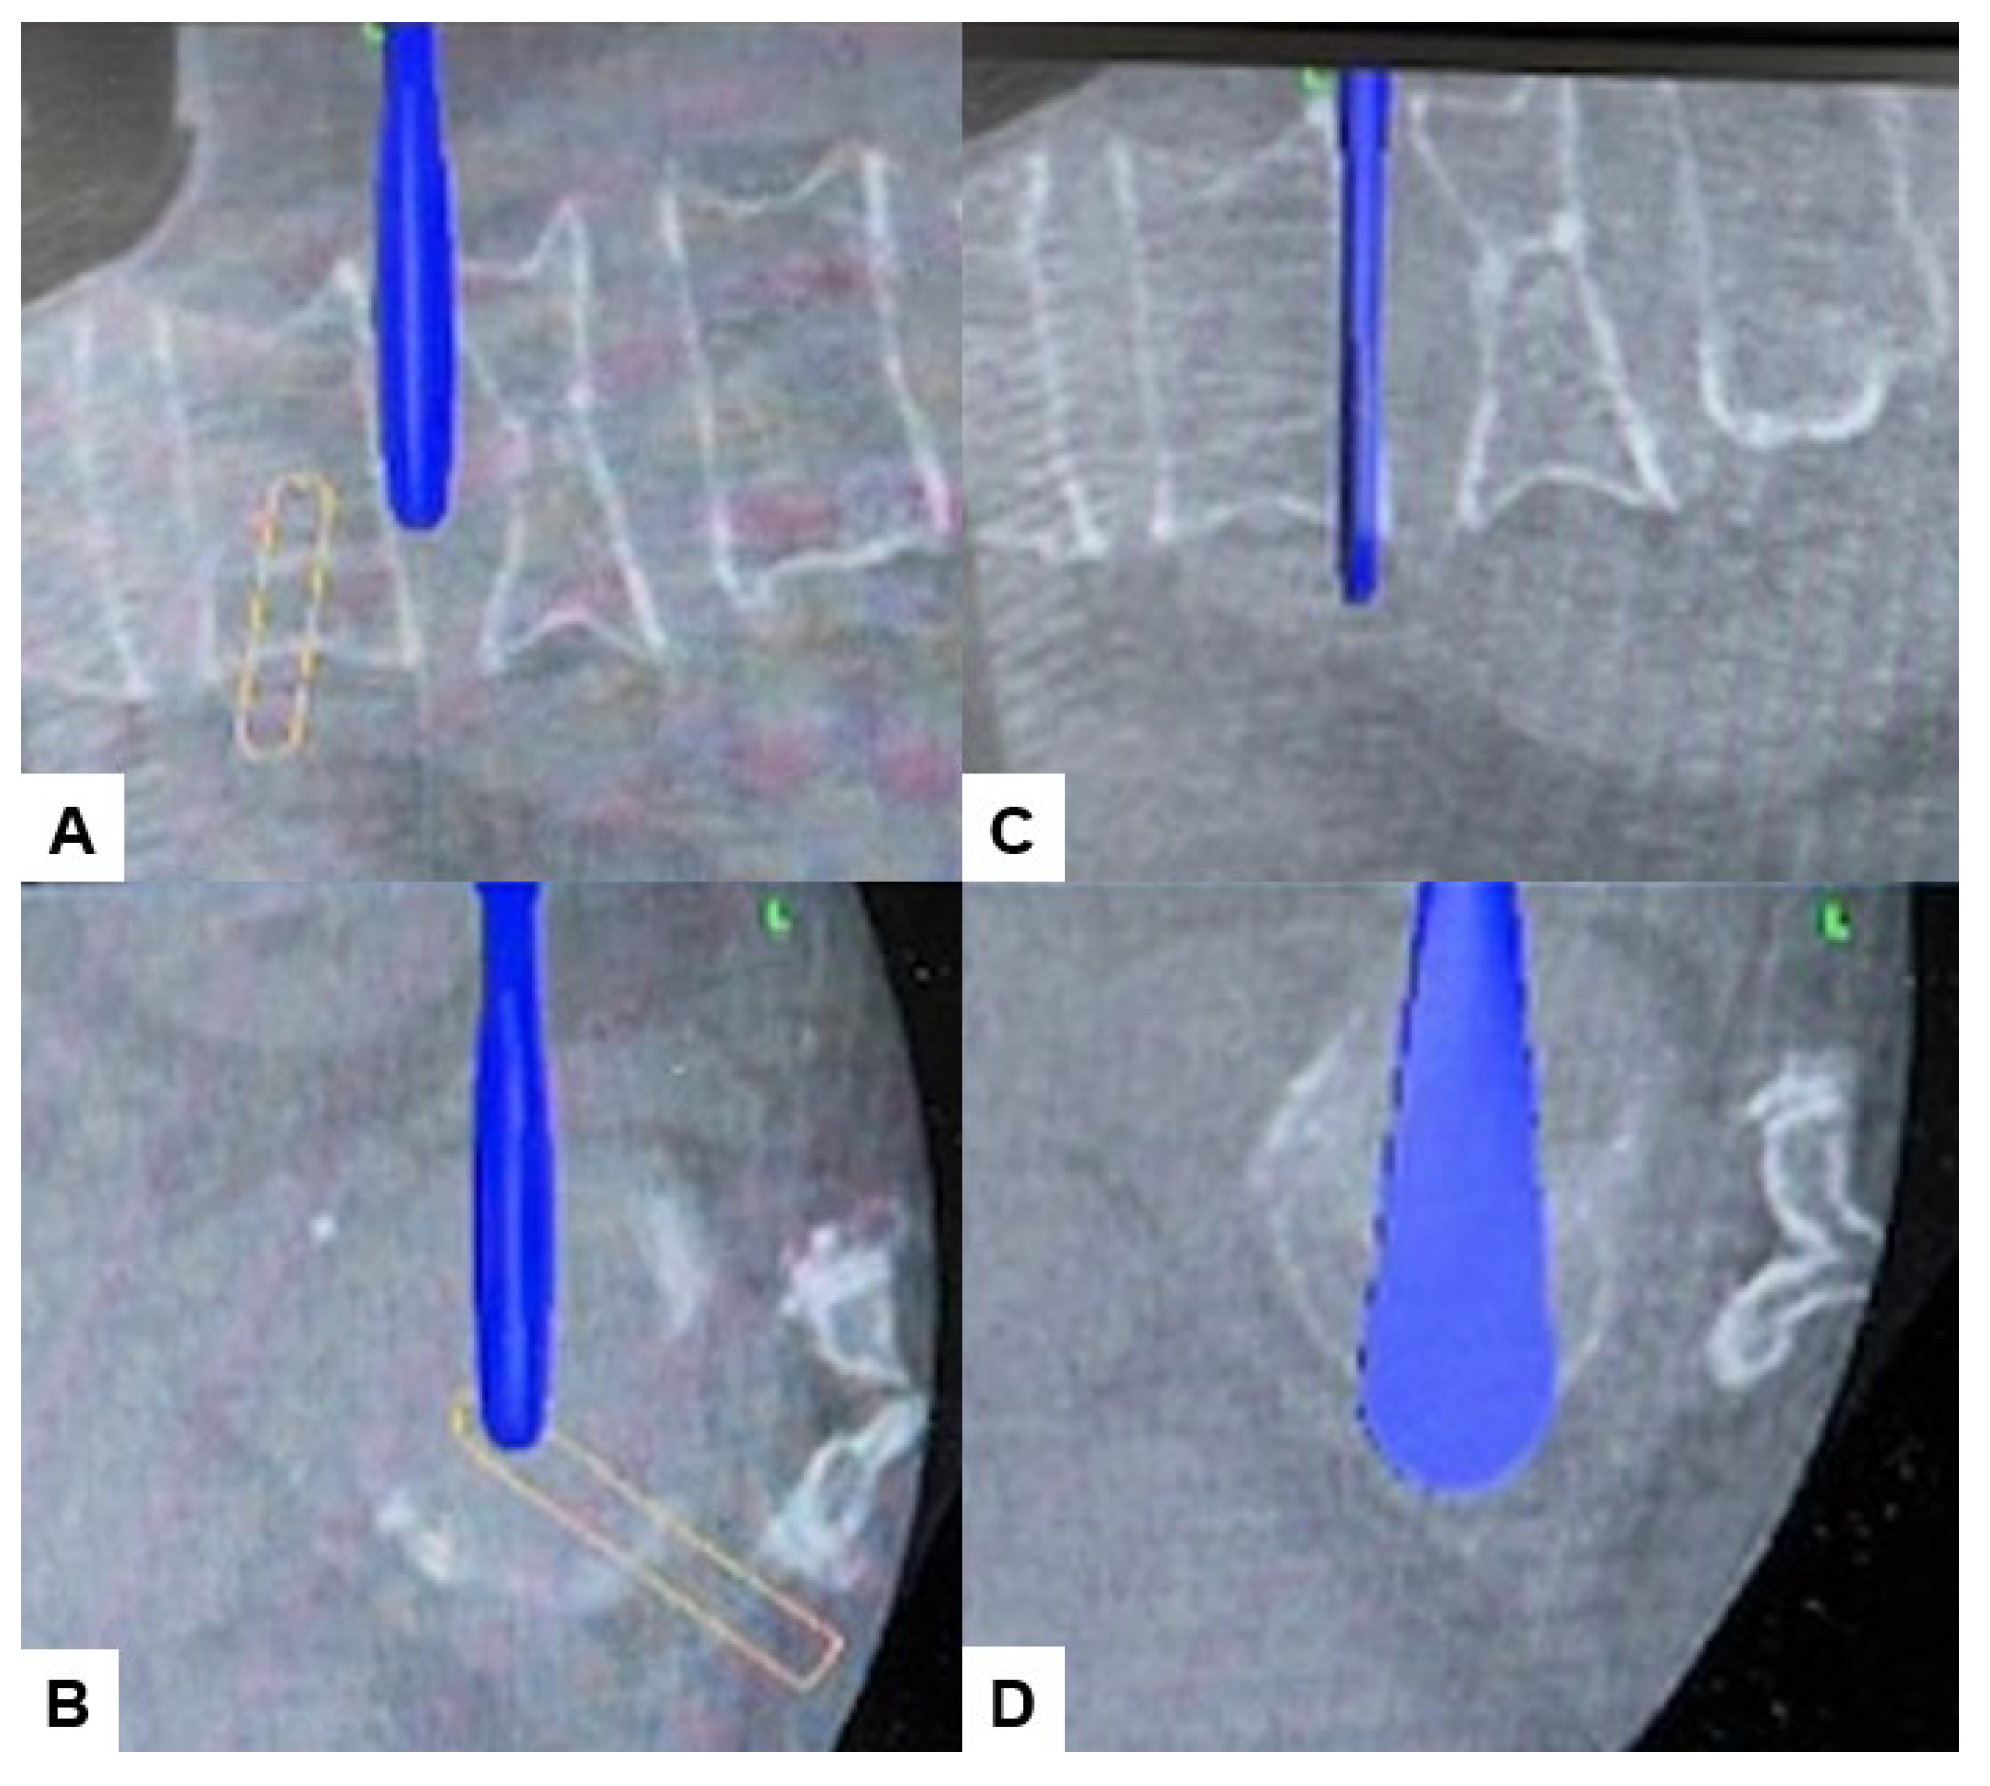

2.4. Surgery